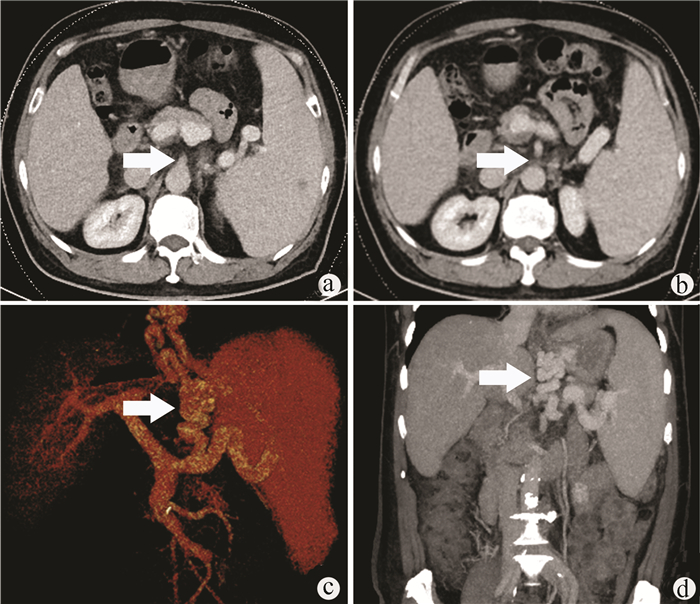

肝滤泡树突细胞肉瘤1例报告

李晨光, 贾继尧, 孙栾彪, 高硕徽

2022, 38(1): 174-176. DOI: 10.3969/j.issn.1001-5256.2022.01.029

摘要(1615) HTML (456) PDF (2854KB)(68)

摘要: